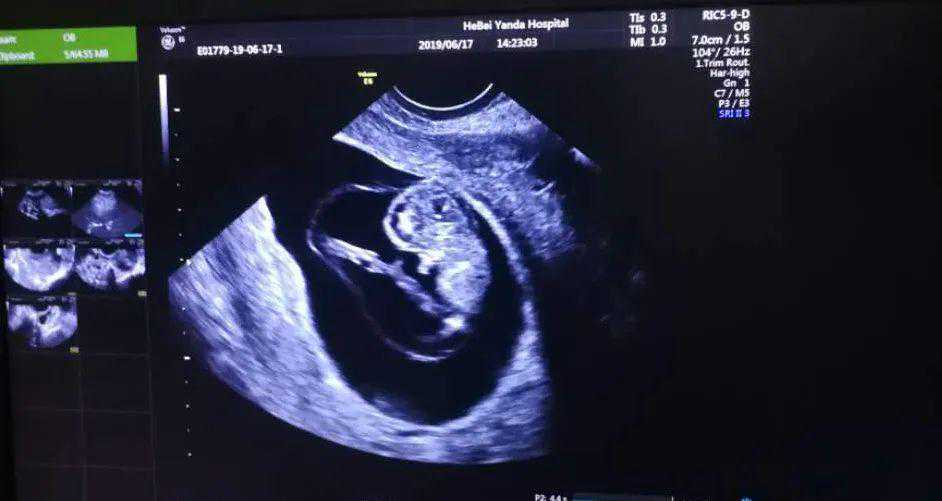

在完成一般检查后,利用促排药,诱导优势卵泡后,适时人工授精,毫无不适,休息半小时后离院,14天后,娟子怀着惴惴不安的心情来到医院,没想到等到了期待已久的“双杠”,紧接着血值翻倍良好。当还沉浸在幸福的喜悦中时,却在2周后出现腹痛、阴道少量出血,超声提示:宫角妊娠、胎停育,妇科拟腹腔镜手术。

经检查,田主任认为孕囊仅仅靠近宫角,尚可在宫腔镜探查下轻柔清宫术。果然,在田主任的精心操作下,顺利地完成了清宫术,同时也找到胚胎着床位置异常的原因,那就是子宫内膜炎。

在历经3个月的调整休复等治疗后,再次人工授精助孕成功。如今,她的宝宝已经顺利出生啦!